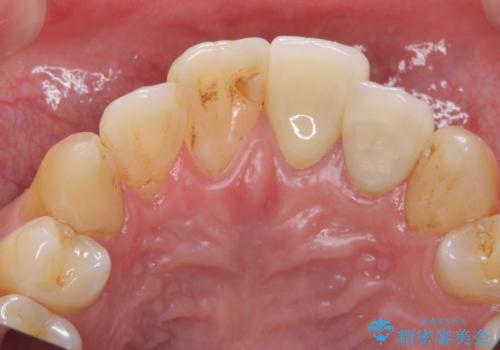

- 前歯の突出を主訴に来院。

全体矯正を行うとなると健康な歯を4本抜歯することになるため、歯は抜かず上だけの部分矯正で最小限で前歯を整えることにしました。

前歯は少し細く削って前に出ないように整えました。

左上の1番目の前歯は神経を取ってある歯でした。今後変色もすすんでいくため、治療のやり直しを行いセラミックでかぶせました。

左上の2番目の前歯は虫歯治療を行い、神経治療まで行っています。